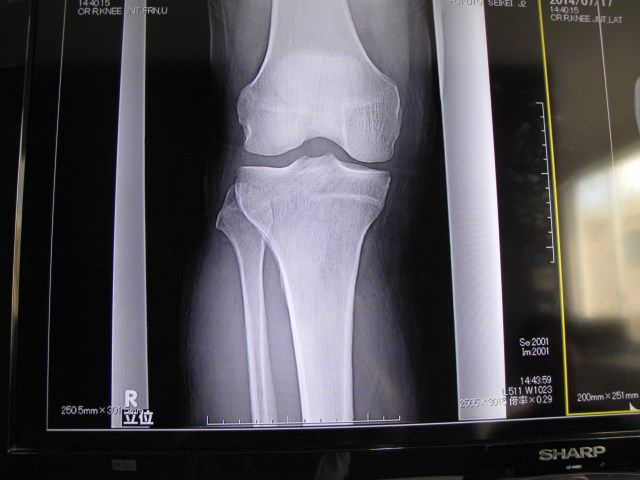

What fun! A visit to a Japanese medical clinic is always worthwhile, if not for the treatment, then for the experience. I do not mean to say that the treatment is bad – on the contrary – but more that each visit is an adventure. First, I have an X-ray.